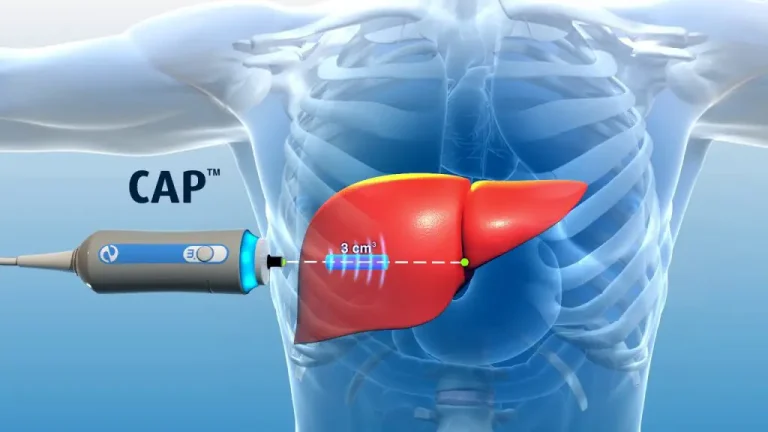

بیمارستان آرمان دارای بخش های جراحی عمومی ، زنان ، ارتوپدی ، جراحی مغز و اعصاب ، زیبایی ،داخلی، بلوک زنان، نوزادان، آی سی یو جنرال ، آی سی یو نوزادان ،آزمایشگاه ، رادیولوژی، سی سی یو ، سی تی اسکن ۱۶ اسلایس ، تصویربرداری، سونوگرافی ، ماموگرافی ، تراکم استخوان، فیزیوتراپی ، شنوایی سنجی و گفتار درمانی ، کلینیک تغذیه ، کلینیک پوست و مو ، اسکوپی، داروخانه می باشد.

بیمارستان آرمان در خرداد ماه 1398 درجهت ارائه خدمات مطلوب و مورد نیاز جامعه افتتاح گردید .بیمارستان آرمان با دو هزار متر مربع زمین ، زیر بنای 8440 متر مربع و 100 تخت دارای 198 پزشک سهامدار و 247 پزشک مهمان می باشد. بیمارستان آرمان دارای بخش های جراحی عمومی ، زنان ، ارتوپدی ، زیبایی ،داخل، بلوک زایمان، زنان نوزادان ، آی سی یو جنرال ، آی سی یو نوزادان ،آزمایشگاه رادیولوژی، سی سی یو ، سی تی اسکن 16 اسلایس ، سونوگرافی ، ماموگرافی ، تراکم استخوان، فیزیوتراپی ، شنوایی سنجی و گفتار درمانی ، کلینیک تغذیه کلینیک پوست و مو ، داروخانه می باشد .